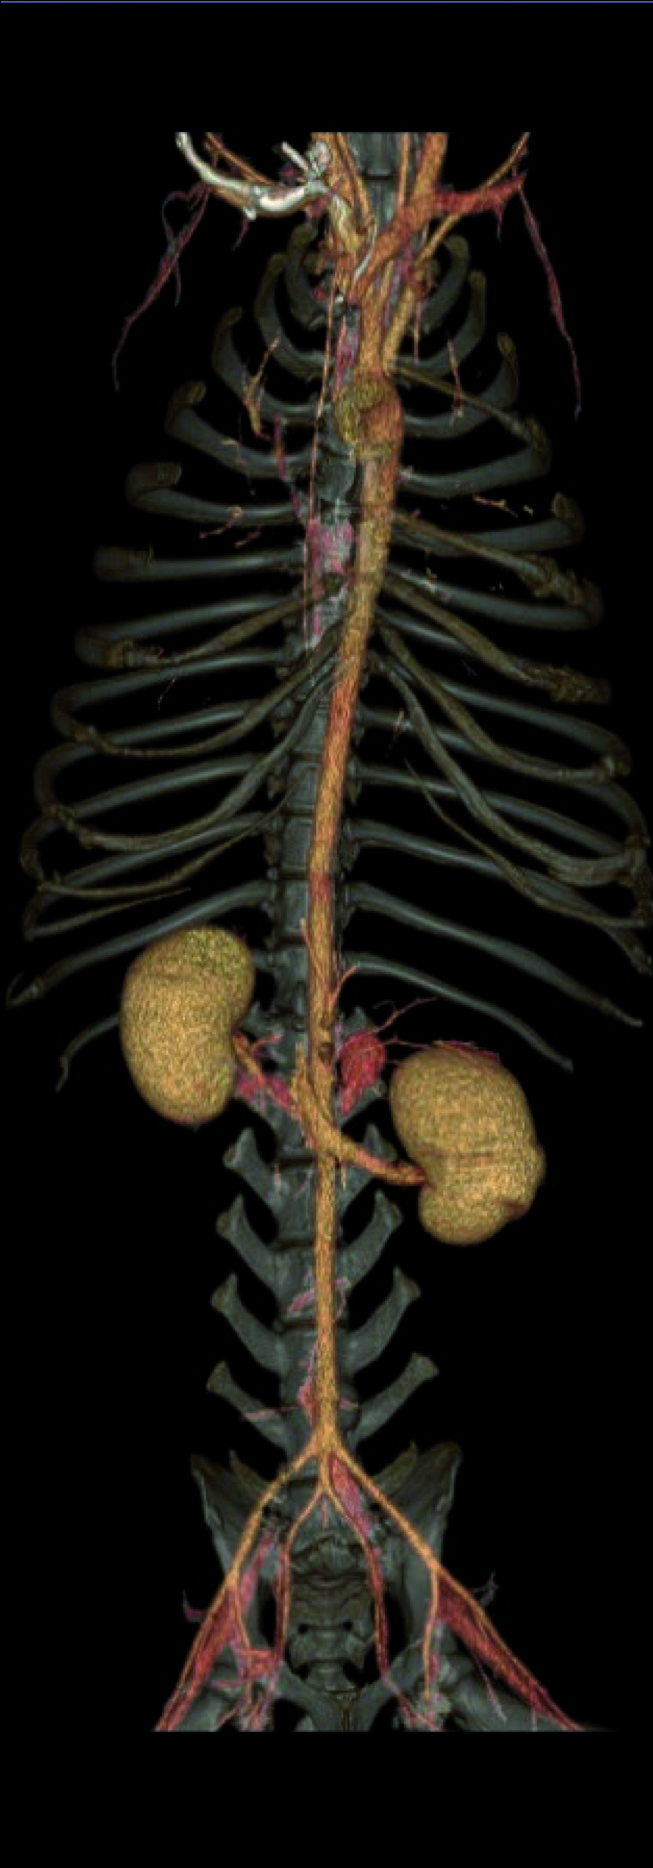

La tecnologia è stata sviluppata pensando agli esseri umani, ma la sua compattezza e il costo contenuto – abbinate a ottime funzionalità di base – l’hanno resa una soluzione particolarmente adatta anche alle necessità dell’ambito veterinario. Oltre a una migliorata risoluzione spaziale, la nuova tecnologia garantisce diagnosi più accurate e meno invasive grazie a software innovativi che consentono l’ottimizzazione della dose di radiazioni erogate, la visualizzazione in 3D delle immagini esaminate, l’analisi automatica dei vasi, l’endoscopia virtuale e la colonografia TC.

I vantaggi sono molteplici: un esame TC consente di valutare al meglio la presenza di eventuali metastasi, di studiare i margini di masse per preparare al meglio un eventuale intervento operatorio o, mediante l’utilizzo di mezzi di contrasto specifici, di diagnosticare problemi vascolari potenzialmente non esplorabili con altre metodiche di imaging.